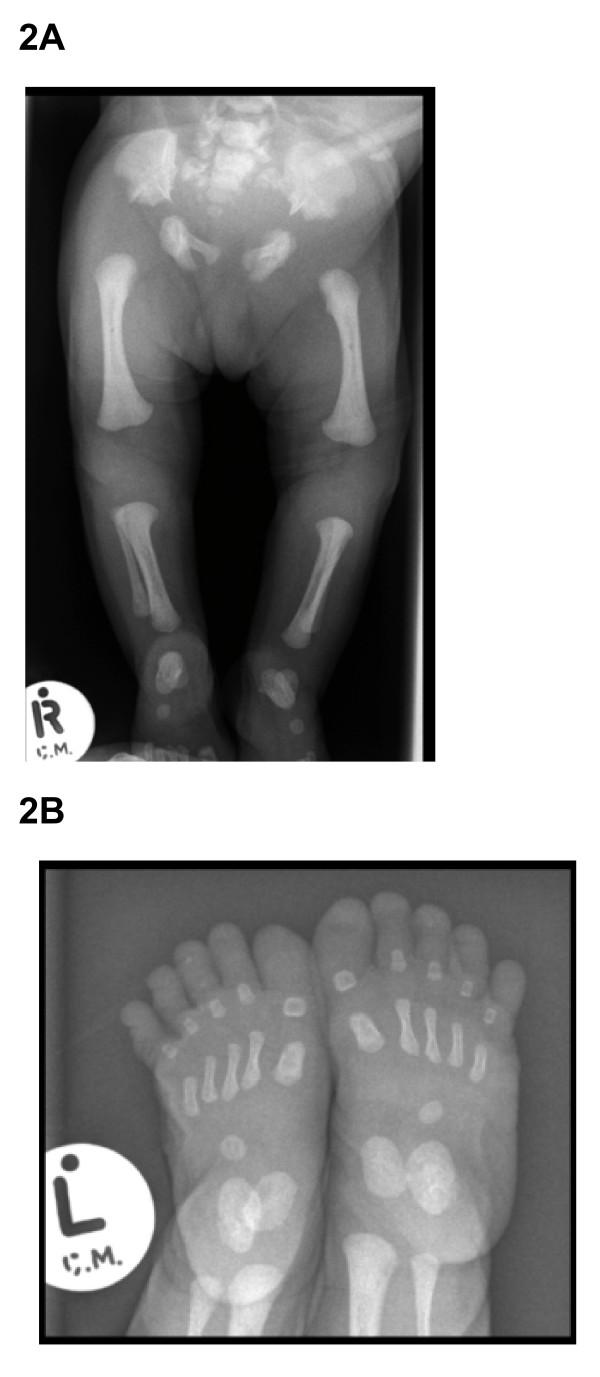

Ellis-van Creveld (EvC) syndrome is an autosomal recessive chondrodysplastic condition with clinical manifestations that include short-limbs and ribs, postaxial polydactyly and dysplastic nails and teeth. In about two thirds of patients, mutations in either EVC or EVC2 genes have been found to be the underlying cause.

All the children had the common clinical and radiological features of this syndrome. However, DNA sequence analysis of the genes shown to be involved (EVC and EVC2) revealed a novel splice site mutation (c.2047-1G>T) in intron 13 of EVC2 gene in one family. In addition, we confirm previous mutational analyses that showed a truncating mutation in exon 13 of EVC gene (c.1813C>T; p.Q605X) in the second family and a single nucleotide deletion (c.981delG; p.K327fs) in exon 8 of EVC2 gene in the third family. No mutations in the exons, splice sites or the promoter regions of either gene have been found in the index case of the fourth family who exhibited "EvC-like" features.